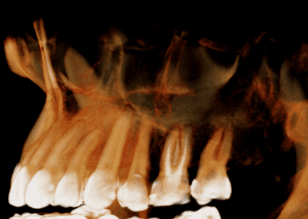

左上第一小臼齒蛀牙缺損 齒質蛀牙嚴重導致斷裂,骨頭破壞需植入牙根時補骨促進骨整合 待3個月後骨整合完